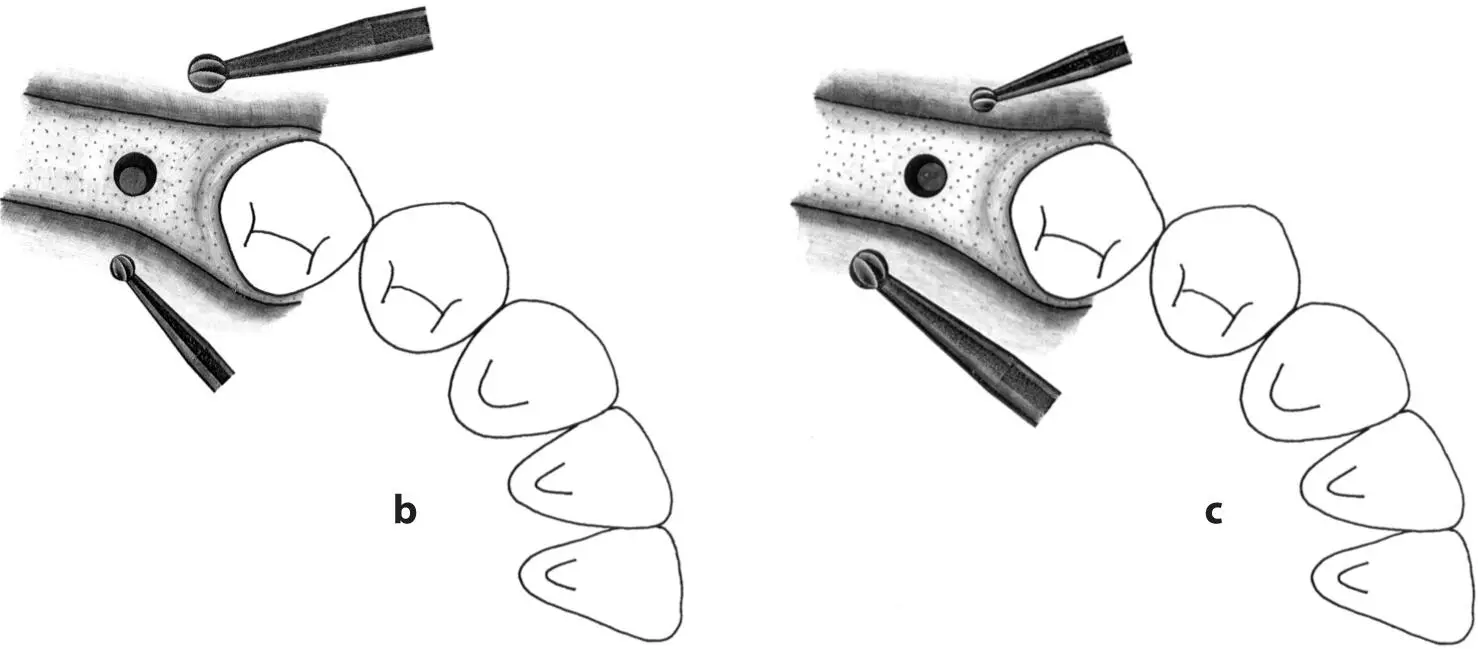

Fig 1-3Correction of the position and axis of the implant site preparation.

Fig 1-3a The preparation of the implant site begins with the use of the nos. 1 and 2 round burs to mark the position of the implant site.

Figs 1-3b and 1-3c Any required changes to the marking made with the first round bur can be accomplished with the no. 2 round bur, as shown in this occlusal view. These initial steps for the preparation of the implant site ensure the correct implant position orofacially and mesiodistally.